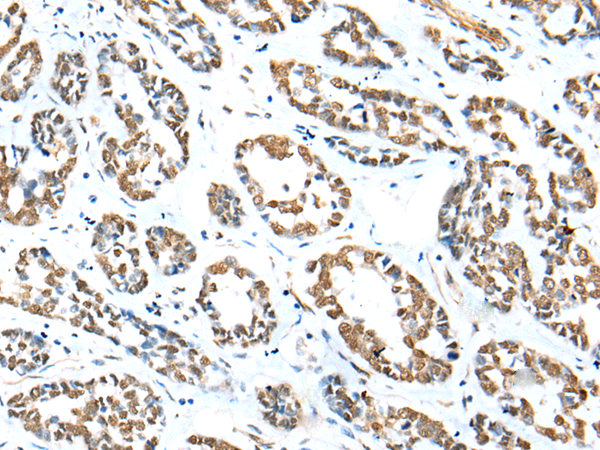

ZNF248 belongs to the krueppel C2H2-type zinc-finger protein family. It contains 8 C2H2-type zinc fingers and 1 KRAB domain. ZNF248 may be involved in transcriptional regulation.

ELISA, IHC

IHC positive control:

IHC Recommend dilution:

20-100